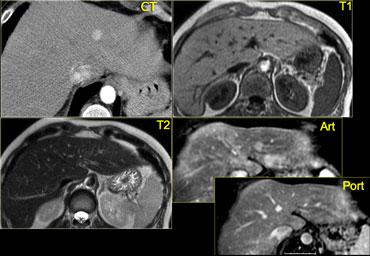

Bên trái là tổn thương không điển hình, biểu hiện giảm sinh mạch trên CT, có thể là di căn.

Cùng ca bệnh trên MR động học.

Lưu ý cách MR thể hiện rõ kiểu ngấm thuốc ngoại vi dạng nốt, lan dần vào trung tâm (mũi tên cong màu xanh) mà CT không thể hiện được.

Bên trái là tổn thương giảm âm không điển hình, được bao quanh bởi một quầng sáng nhỏ nhưng rõ ràng.

Trong pha động mạch, có ngấm thuốc đồng nhất với cường độ động mạch, thường gặp trong u máu nhỏ.

Trong pha tĩnh mạch cửa và pha cân bằng, tổn thương có cùng mức độ ngấm thuốc như động mạch chủ.

Như vậy, tất cả các đặc điểm đều phù hợp với u máu, một tổn thương mạch máu lành tính, không phải tổn thương đặc.